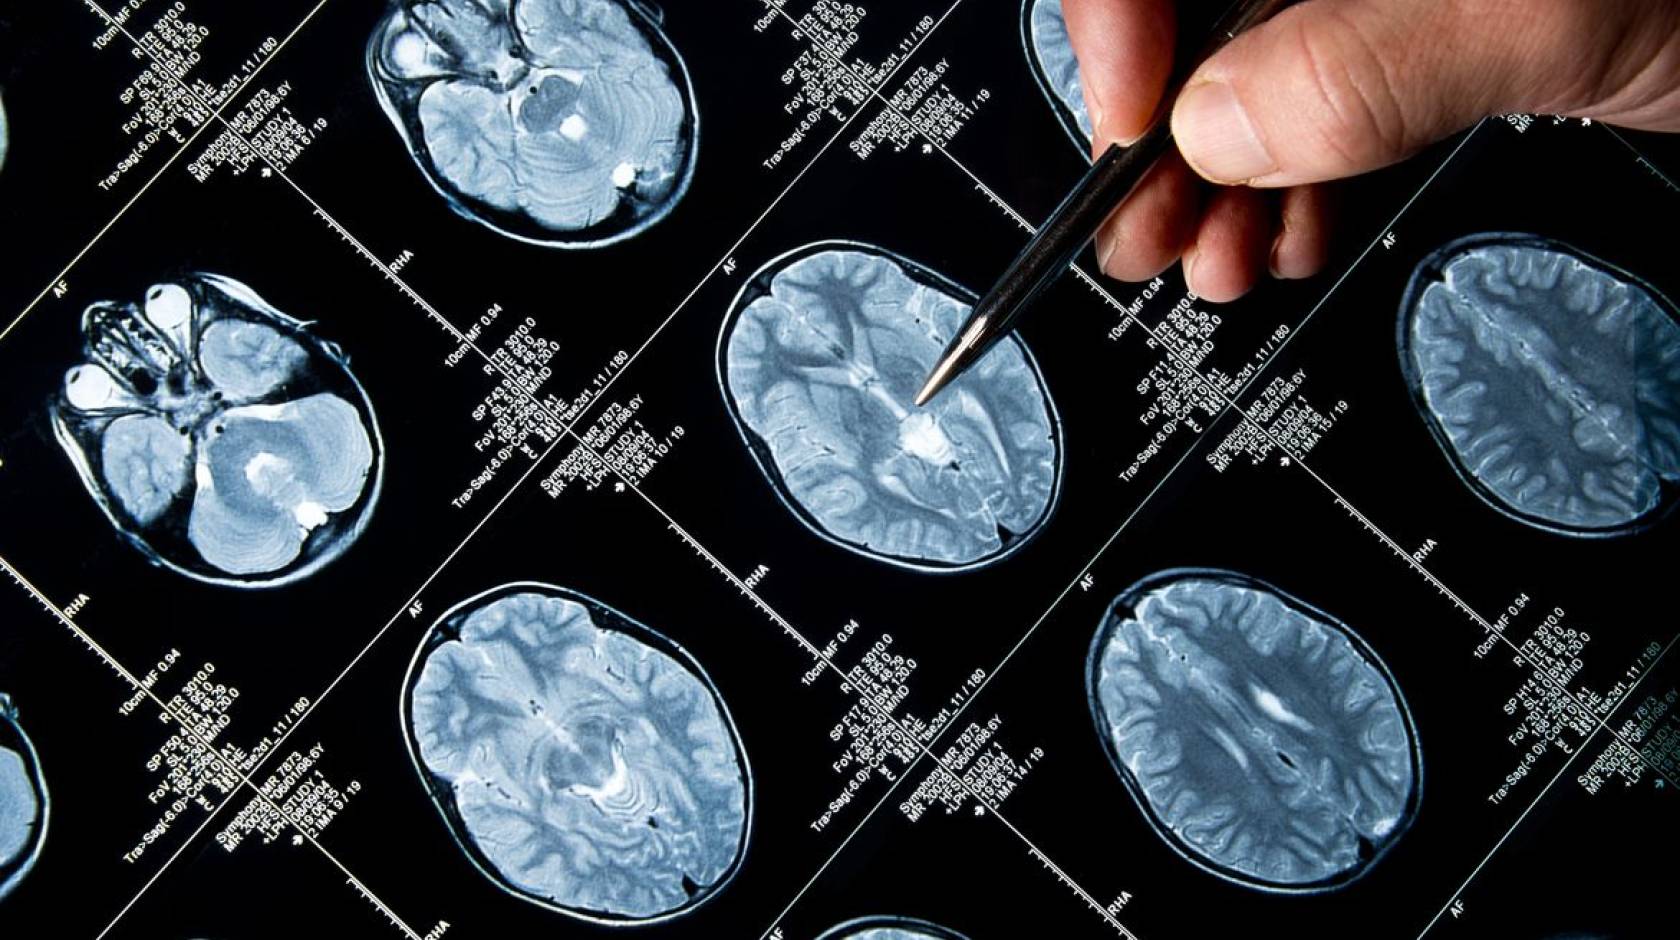

Benjamin Ellingson, director of the UCLA Brain Tumor Imaging Laboratory and a member of the Jonsson Cancer Center, was a key participant in the research that led to the clinical trial. He was involved in the radiographic evaluation of tumors in the study, which confirmed that there was a benefit of the targeted therapy. The study’s first author is Dr. Ingo Mellinghoff of Memorial Sloan-Kettering Cancer Center. The co-senior author is Dr. Patrick Wen of the Dana-Farber Cancer Institute.